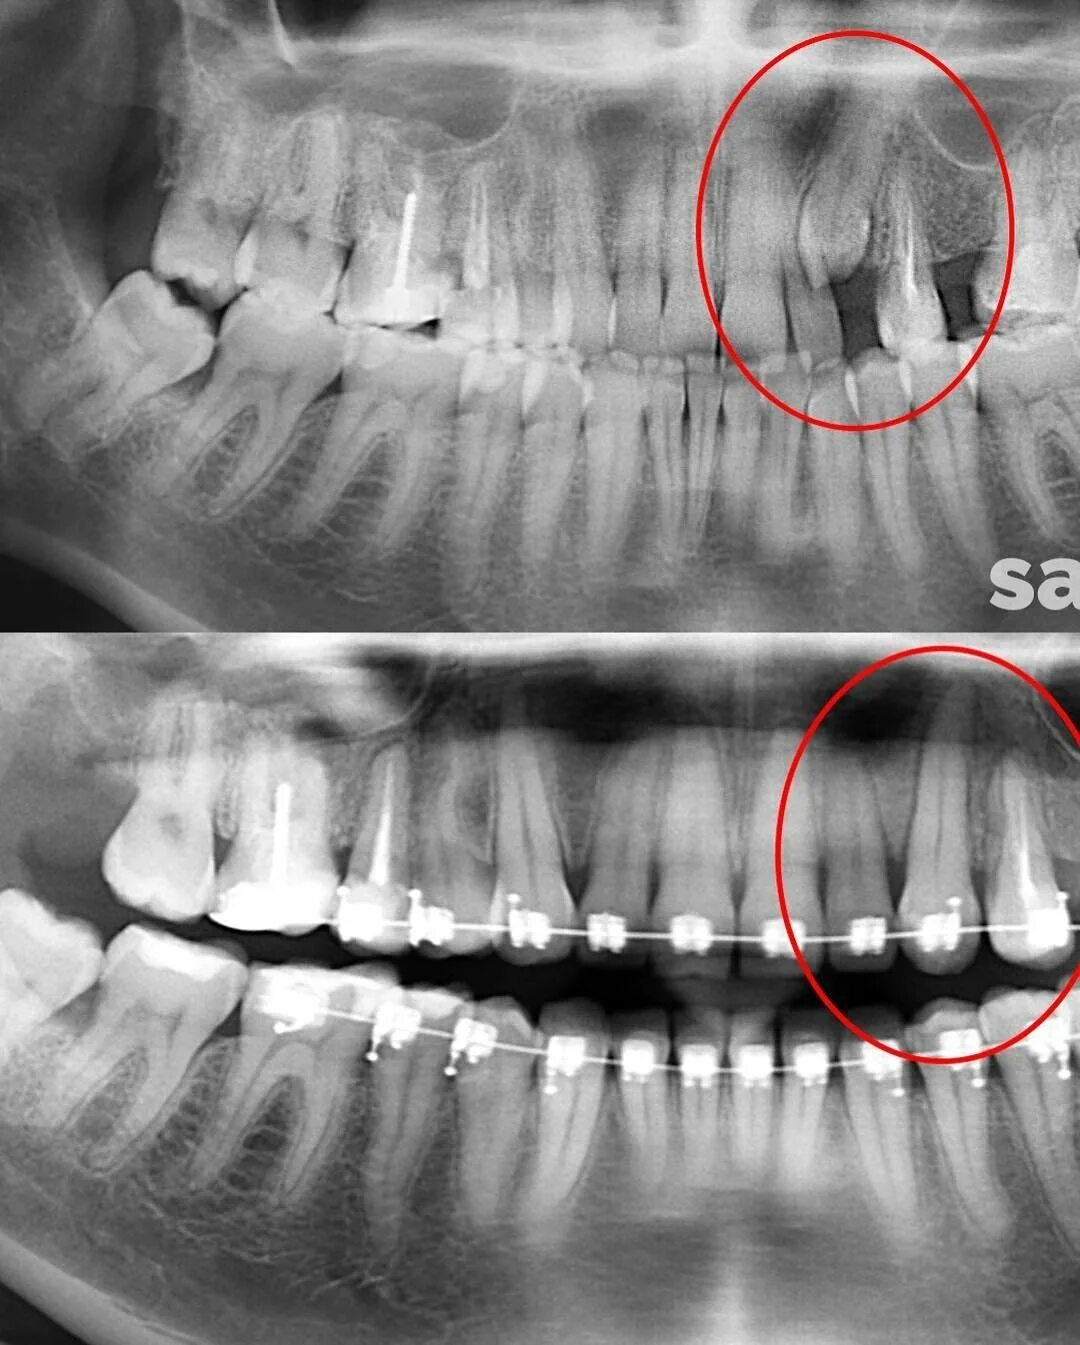

Удалить 7 зуб сверху